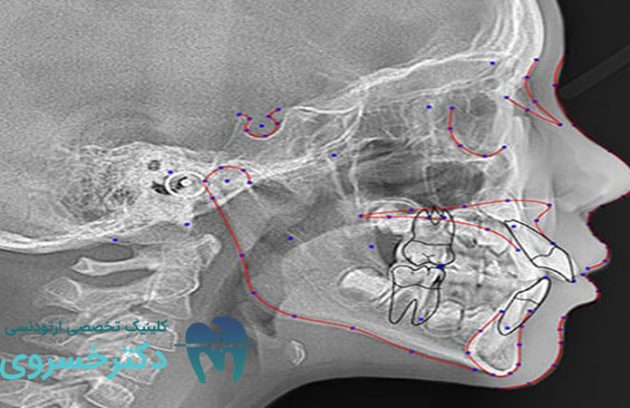

نقش سفالومتری در ارزیابی مشکلات ارتودنسی